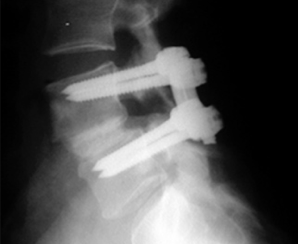

Röntgenfoto's worden vaak gemaakt en meestal in staande positie. Dit is bedoeld om de mate van slippen te 'beoordelen' en om te bepalen welk type spondylolisthese aanwezig is.

Wervelkolomchirurgie kan een rol spelen bij de behandeling en dit zal meestal een fusie-operatie met bottransplantaat inhouden. Als er zenuwpijn aanwezig is, kan deze tegelijkertijd gedecomprimeerd worden. Er zijn veel verschillende variaties op de operaties die worden uitgevoerd en de details van een eventuele operatie kunnen het beste met uw arts worden besproken.